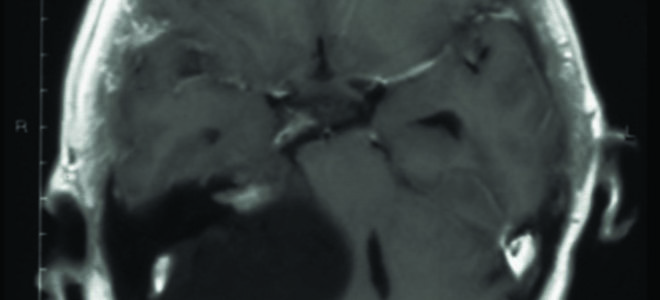

Невринома слухового нерва: симптомы, лечение и удаление

В мировой литературе используется в основном термин «вестибулярная шваннома», а в отечественной «невринома слухового (VIII) нерва».